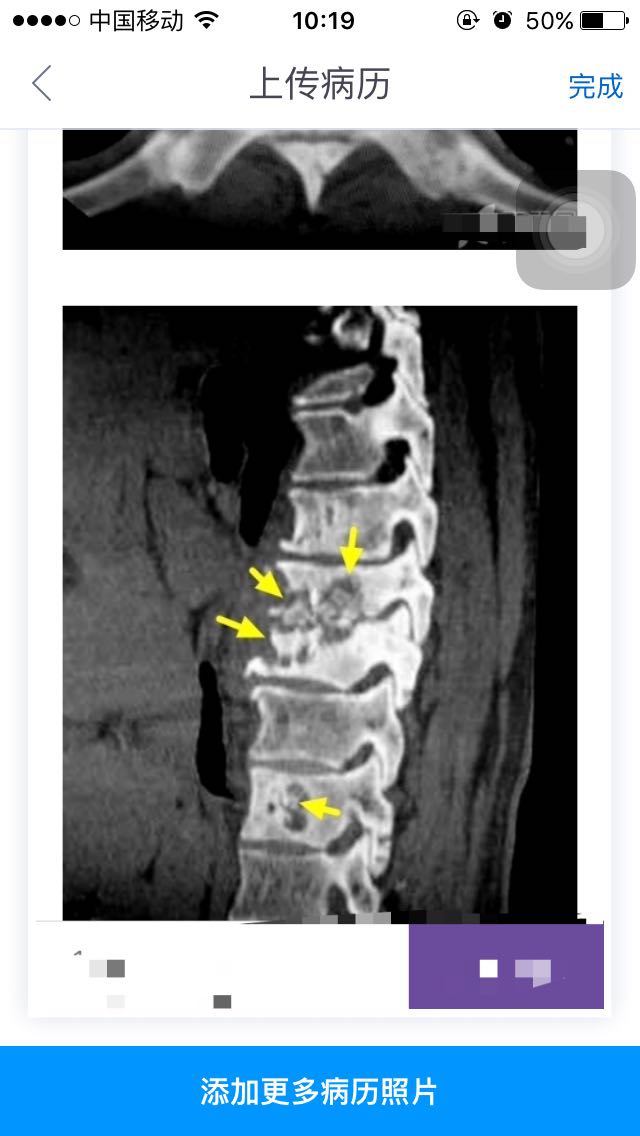

查体下肢已无感觉运动。行PET-CT结果考虑结核病灶并未见肿瘤性质病损,考虑胸8、9椎体结核,胸7、11、腰2考虑良性病变。CT、MRI均考虑转移瘤。红细胞沉降率34mm/h,肿瘤指标为糖类抗原12-5 34.43U/l(小于35)。体重消瘦约7kg,半年。无明显乏力、纳差、午后低热。 影像表现:多发胸椎骨质破坏,其内可见死骨(黄箭)。邻近椎间隙变窄,椎旁软组织增厚,CT示内部有液体密度区,MRIT1呈略低信号,T2成高信号。符合冷脓肿(白箭)。